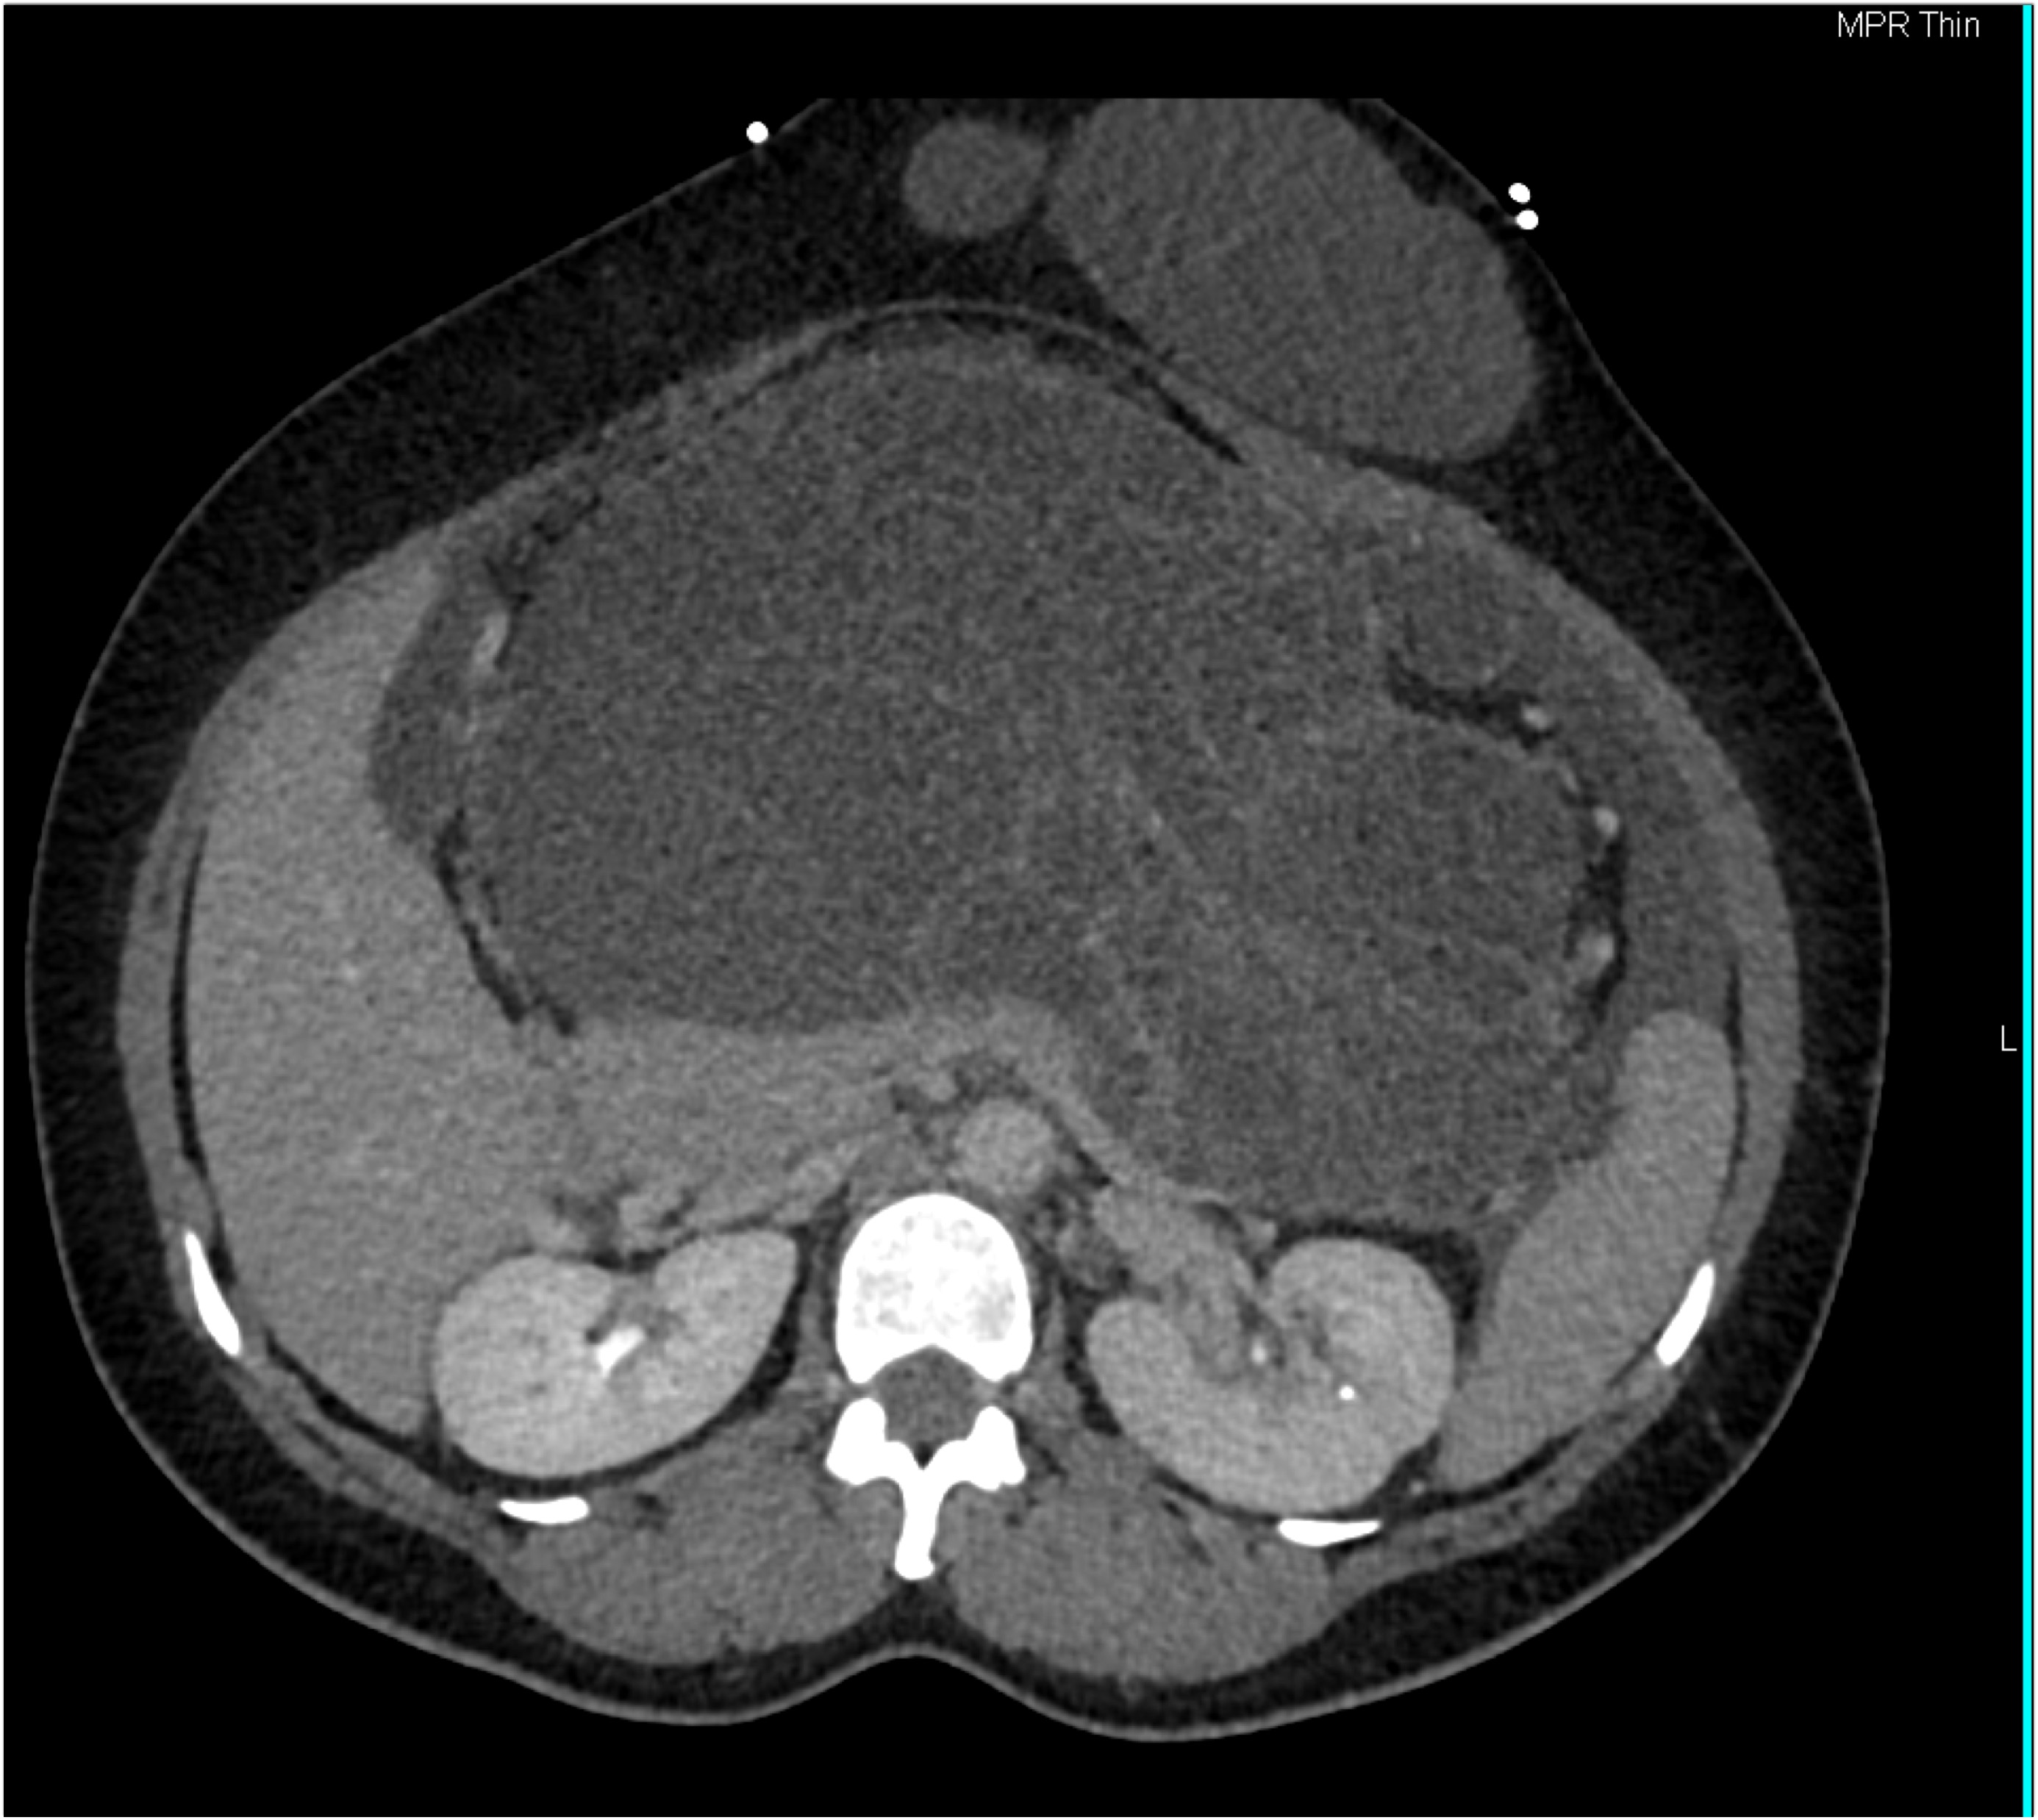

3) The most likely diagnosis in this case is?

hepatoma

cholangiocarcinoma

gallbladder cancer

hepatic adenoma